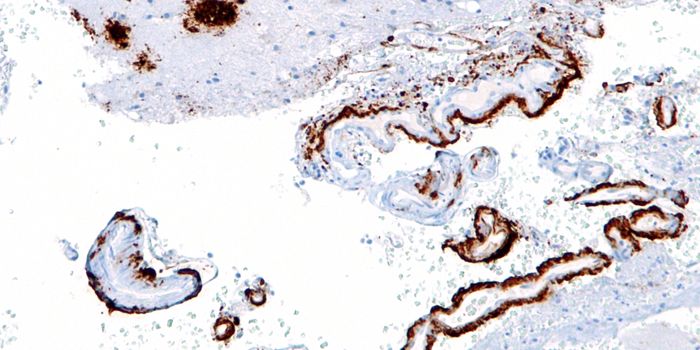

MAR 18, 2016Health & MedicineScientists have developed a brain implant that can turn the patient’s immune system against Alzheimer’s dise ...